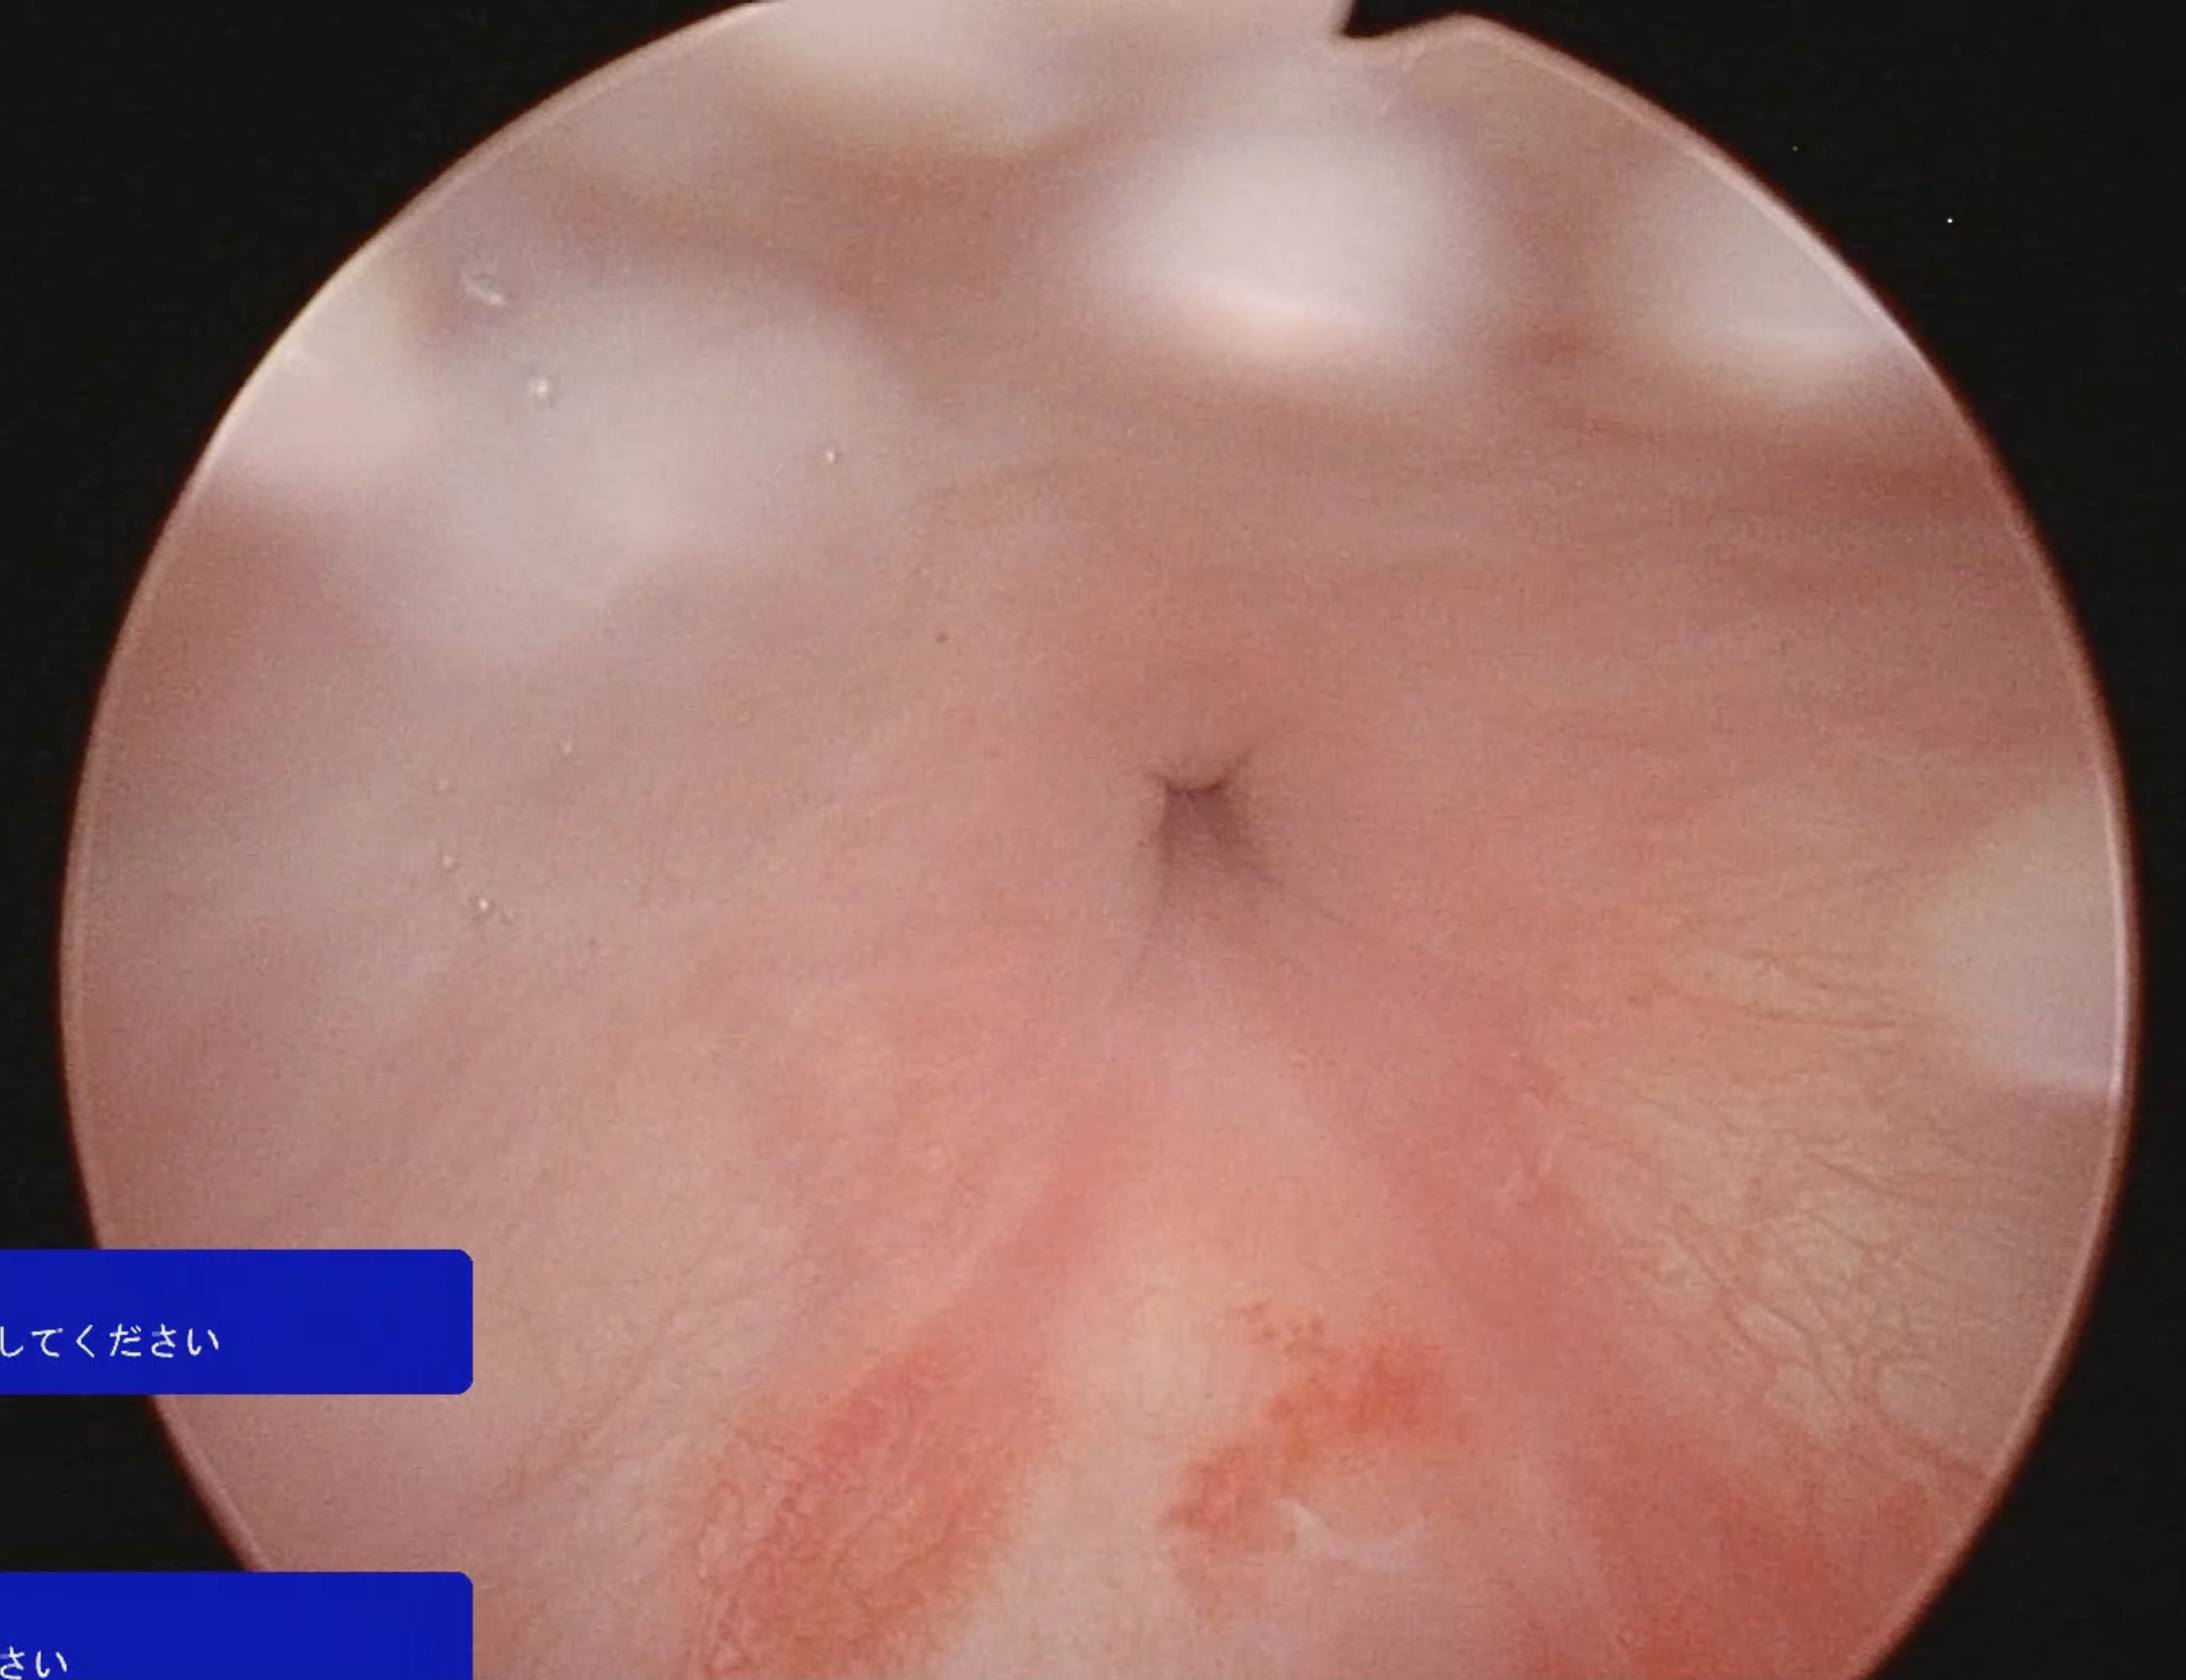

結石除去後の膀胱内

中央に見える穴は尿道